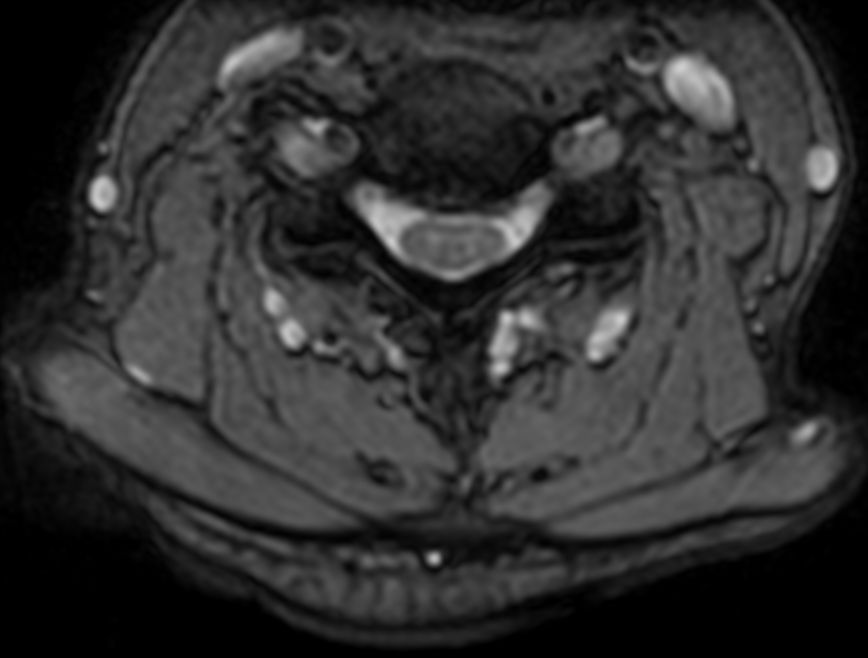

T2w TSE with ComforTone